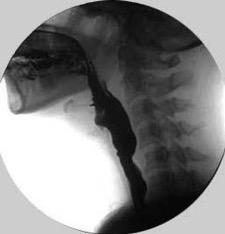

2. Modified Barium Swallow Study (Videofluoroscopy)

• The patient swallows food and liquids containing barium of different consistencies, and the process is recorded radiologically.

• The passage of food through the esophagus, pharynx, and larynx, as well as any pauses, obstructions, or aspiration risks, is observed in detail.

• This method is used to evaluate both the overall swallowing function and the structural condition of the esophagus.

• Radiation is used during the procedure, so time and dose are limited, but it provides very detailed anatomical and functional information.